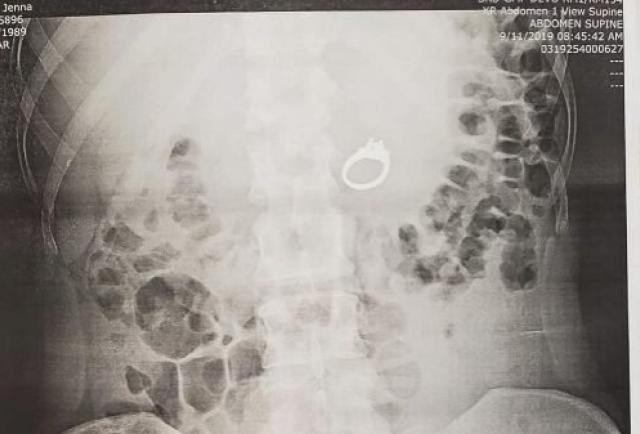

El anillo estaba alojado en el estómago de la fémina.

Después del percance, los novios acudieron a urgencias para que les den una explicación de lo sucedido. El médico le realizó a Evans los exámenes pertinentes y una radiografía donde se pude demostrar que el anillo estaba alojado justo en su estómago. “Definitivamente podía sentirlo en mis entrañas, estaba empezando a doler mucho y nos ponía nerviosos”, dijo la joven.